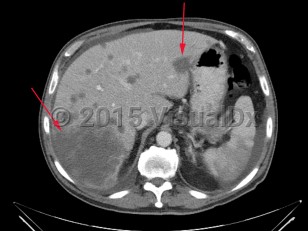

Liver cancer refers to a malignancy that arises primarily within the liver. There are several types of liver cancers. Hepatocellular carcinoma, accounting for approximately 75% of primary liver cancers, is due to malignant transformation in hepatocytes. This is most commonly seen in patients with cirrhosis of any etiology (eg, chronic viral hepatitis, alcohol-related liver disease, nonalcoholic steatohepatitis). Cholangiocarcinoma is the second most common primary liver cancer, accounting for approximately 10%-20% of cases. This is a cancer of bile duct origin.

There are several rare types of liver cancer. Angiosarcoma and epithelioid hemangioendothelioma arise from mesenchymal cells. Intraductal papillary neoplasm and mucinous cystic neoplasm with invasive carcinoma arise from the bile ducts.